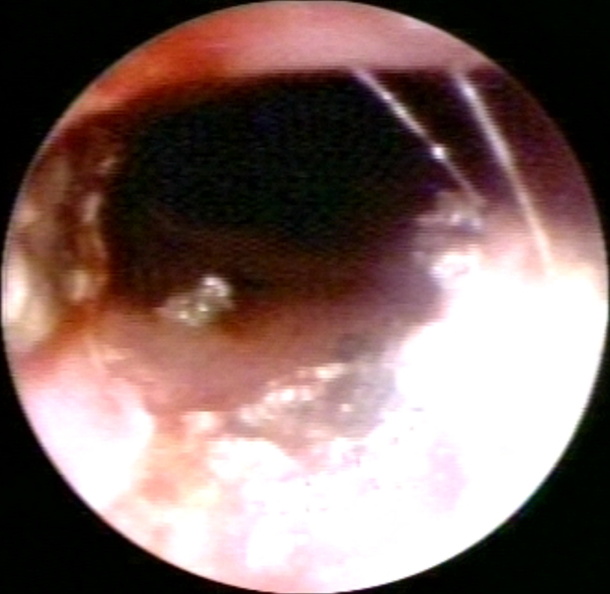

ENDOSCOPY: GASTROINTESTINAL: GI: ESOPHAGUS: CARCINOMA,SQUAMOUS;ESOPHAGUS,LASER THERAPY; A1RN ESO CA.9,TUMOR BREAKTHROUGH